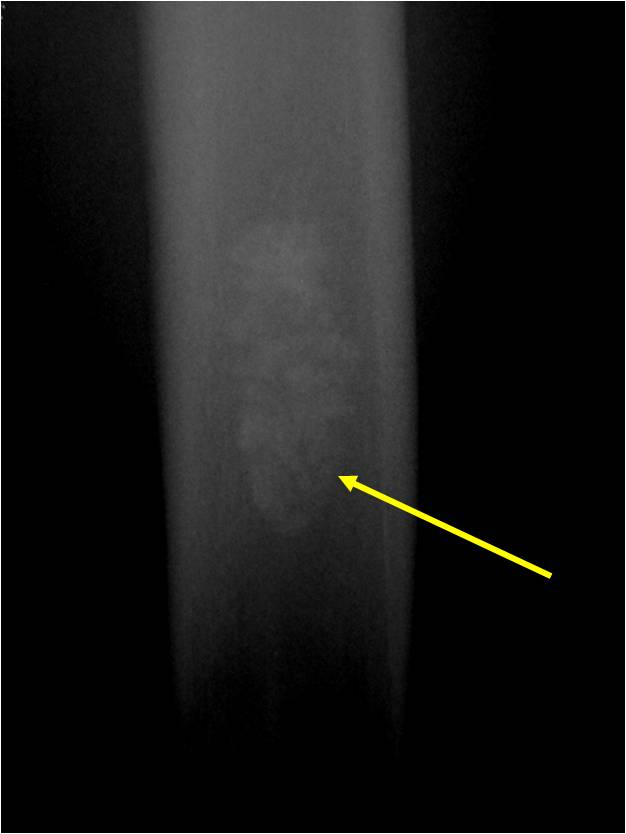

- Localized, radiolucent defect usually with punctate calcifications

- Calcifications are typical but not always present

- Matrix may demonstrate various degrees of calcification

- Calcifications are stippled, punctate, popcorn like calcifications and “Ring and Arc” calcifications

- Cartilage tumors grow in a lobular manner. The perimeters of the lobules undergo

- enchondral ossification that may calcify. If the entire perimeter of the lobule calcifies it appears

- radiographically as a “Ring”. If a portion of the perimeter of a lobule calcifies it forms an “Arc” on

- an X-ray.

Plain X-Ray:

- Geographic lytic lesion

- Central often metaphyseal in long bones

- Can be eccentric also

- Expansile remodeling with thinned cortex

- Chondroid matrix with calcifications in majority of tumors

- Approximately 20% have limited or no calcifications